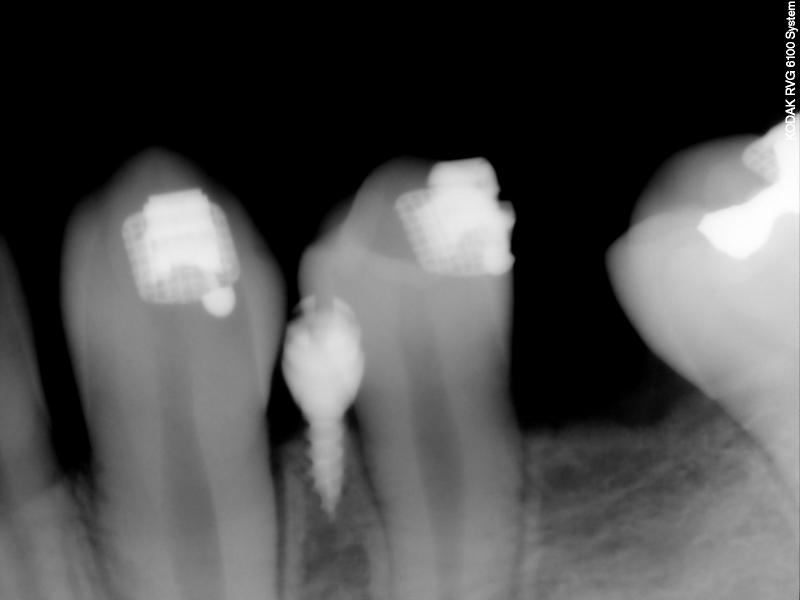

Fig. 5. PA taken (after placing TAD)

© Copyright 2007-2014, Vu Orthodontics. All rights reserved.